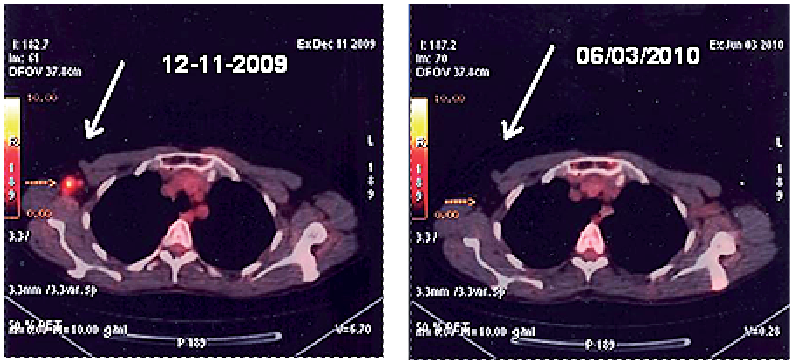

Figure1